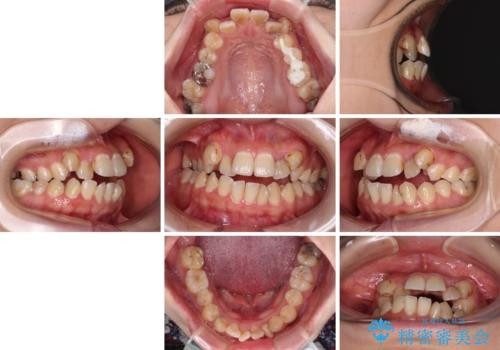

- 上下の歯が非接触であり、八重歯やむし歯を気にして来院された患者様です。

下顎骨の左右偏位はあるものの、上顎骨幅が相対的に狭い状態であったので、奥歯の咬み合わせが非常に乱れていました。

急速拡大装置により上顎骨幅を側方に拡大し、それを利用して八重歯を歯列に納めることにしました。

矯正治療後は全顎的にむし歯が多いため、セラミッククラウンやインレーにより補綴治療を行うこととしました。

急速拡大が奏効し、非抜歯矯正にて八重歯を解決することができました。

矯正治療後半で結婚式を挙げられたそうですが、参列された方々からは綺麗に整った前歯に大変驚かれたそうで、非常に満足されていらっしゃいました。